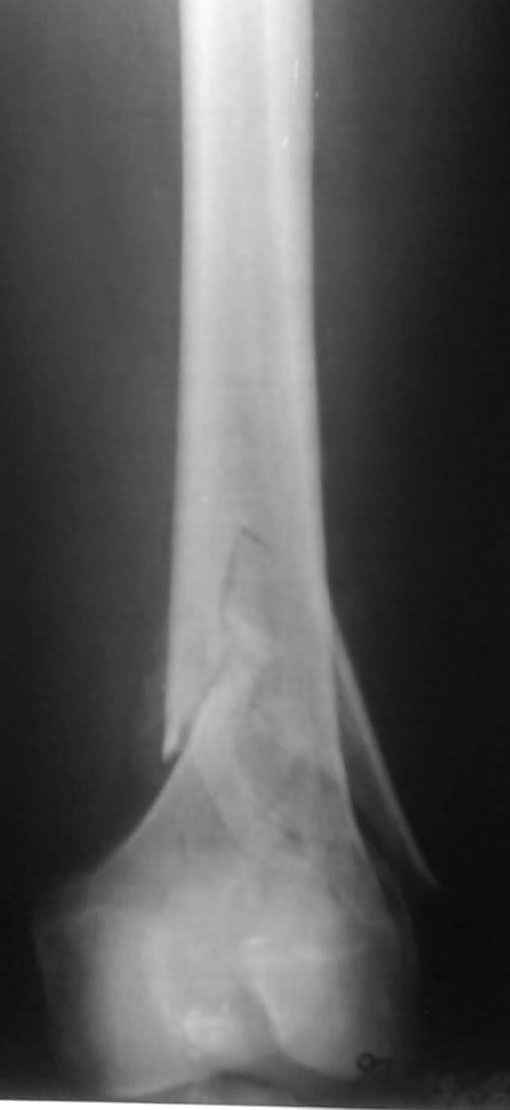

Привет из Нижнего Новгорода! К нам поступил пациент 25 лет с закрытыми переломами обеих бедренных костей, прошел месяц после травмы. Слева - внутрисуставной перелом, поэтому выбор здесь очевиден, открытая репозиция, стабильная фиксация, скорее всего LCP DF, а справа - мнения учёных, как говорится, разошлись. Лично я, как лечащий врач, за закрытый интрамедуллярный остеосинтез DFN. Со мной согласна половина коллектива, другая - за интрамедуллярный остеосинтез (DFN,UFN) но с открытой реопозицией, поскольку при закрытой методике все осколки останутся где-то сбоку, получится дефект и вдруг не срастется!Философский вопрос: что лучше - красивая рентгенограмма или сохранение кровоснабжения? Очень важно мнение коллег! Смирнов Алексей

Мы бы не стали открывать, такие переломы срастаются, хотя бы и с краевым дефектом. То есть если удалять стержень потом, то сильно попозже обычного. В приложении пример. Сразу после операции и через 11 мес. Понятное дело, пациент к тому времени давно и не хромал, и функция колена была полная.